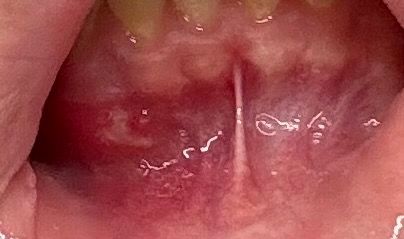

이거 잇몸에 구내염 인가요? 염증인가요?

3일전부터 잇몸에 이런게 생겨있었는데 누르면 아프고 하얗게 생겨서 염증인지 구내염인지 싶어서 질문 남겨 봅니다 병원 가야 할까요?

• 1번 째 사진

구내염은 아니고 잇몸이 전체적으로 염증이 잇는거 같으니 치과에 가셔서 스켈링 및 잇몸치료를 받아보시는게 좋을것같습니다.

사진이 흐려 정확히 보이지 않지만 아마 치아 뿌리 부분이 비춰 보이는 것일 겁니다. 아래 앞니는 주변을 둘러싸고 있는 뼈가 다른 부위에 비해 얇습니다. 따라서 아래 앞니를 보기 위해서 입술을 잡아 당기게 되면 해당 부분의 치아나 뼈 부분이 하얗게 비춰 보일 수 있습니다.

-> 정상적인 구조같습니다.

네 구내염의 양상으로 보이긴 하는데 약국에서 오라메디 등 구내염 연고 발라보고 증상 추이 지켜보고 호전되지 않으면 치과가보세요